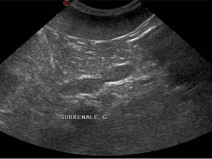

• Échographie de la rate, des surrénales,...(Module satellite C, niveau avancé)

Public visé

La formation est ouverte aux docteurs vétérinaires qui souhaitent offrir au sein des établissements de soin vétérinaire des prestations de qualité accrue en échographie des animaux de compagnie

Prérequis

Être docteur vétérinaire. évoluer dans une structure de soins vétérinaires disposant d’un échographe ou vouée à en disposer dans un proche avenir.

...

• Bases de l’échographie abdominale (module central - niveau de base)

Formation complète

Être docteur vétérinaire. évoluer dans une structure de soins vétérinaires disposant d’un échographe ou...